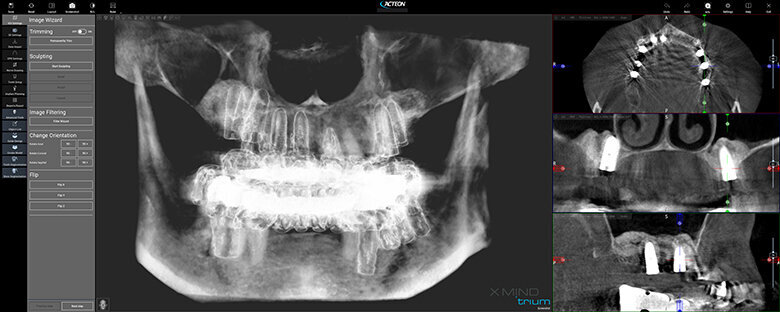

Figure 1 shows a split-mouth case with a bilateral INTRALIFT procedure: after a small crestal “booklet”-flap of approx. 7x7mm is detached, the sinus floor is safely opened with ultrasound Piezotome tips (Figs. 2 & 3), the sinus membrane then detached by the hydrodynamic cavitation effect of the Piezotome-tip TKW5 plugged into the approach canal (Figs. 4 & 5) and the subantral scaffold filled with 2cm of randomly assigned biomaterial (Figs. 6 & 7), followed by wound closure (Fig. 8). After a mean healing period of 8,4 months X-Mind trium CBCT scans were performed, the digital setup of the future bridge constructed with the AIS 3D app and the bone density determined in the sinus-lift site around a virtual implant (Fig. 9). Standardised implants (4mm in diameter and 12mm in length) were then inserted in the position of the virtual implant and insertion torque values (ITV) measured intra-surgically (test groups; Fig. 10). A total of 27 patients with sufficient native subantral crestal bone (min. crest width: 6 mm, height: 12 mm) were screened by X-Mind trium CBCT for bone density with the virtual implant (Fig. 11), the standardised implant inserted and the ITV recorded (control group). Figure 12 depicts the final result after implant insertion in the patient case shown in Figures 1–9.

As can be seen in Fig. 13, the mean CBCT bone density values in Hounsfield units (HU) at the implant site differed significantly (p <0.05) between all four test groups and the control group. The precise numerical HU values are “translated” by AIS 3D app software and are also colour-coded for easier interpretation at first glance: the brighter the green the CBCT voxel matrix shows around the virtual implant, the higher the bone density, with a virtual neutral threshold of 500 HU. Contrary, the more reddish the CBCT voxel matrix around the digital implant is depicted, the worse the biomechanical bone quality (Fig. 14). The corresponding insertion torque values (ITV) of the inserted standardised implant measured at the location of the transcrestal INTRALIFT approach (Fig. 2) also differed significantly between all test groups and the control group. Figure 15 depicts the cumulative result of the correlation between HU and ITV values for all test groups and the control group.

As the presented study proves, contemporary CBCT technology adds another outstanding feature to the general CBCT-based digital workflow as the first and only tool to safely determine the grade of primary implant stability to be expected at each individual implant site already in the planning phase before the treatment or surgery is performed (Fig. 16). By using CBCT-based bone densitometry as an integrated diagnostic step in the digital workflow, the clinician for the first time can decide individually for each patient and each implant site whether an implant insertion with immediate prosthetic loading might bear an unacceptable risk of early or delayed implant loss, and can therefore inform the patient accordingly based on evidence.